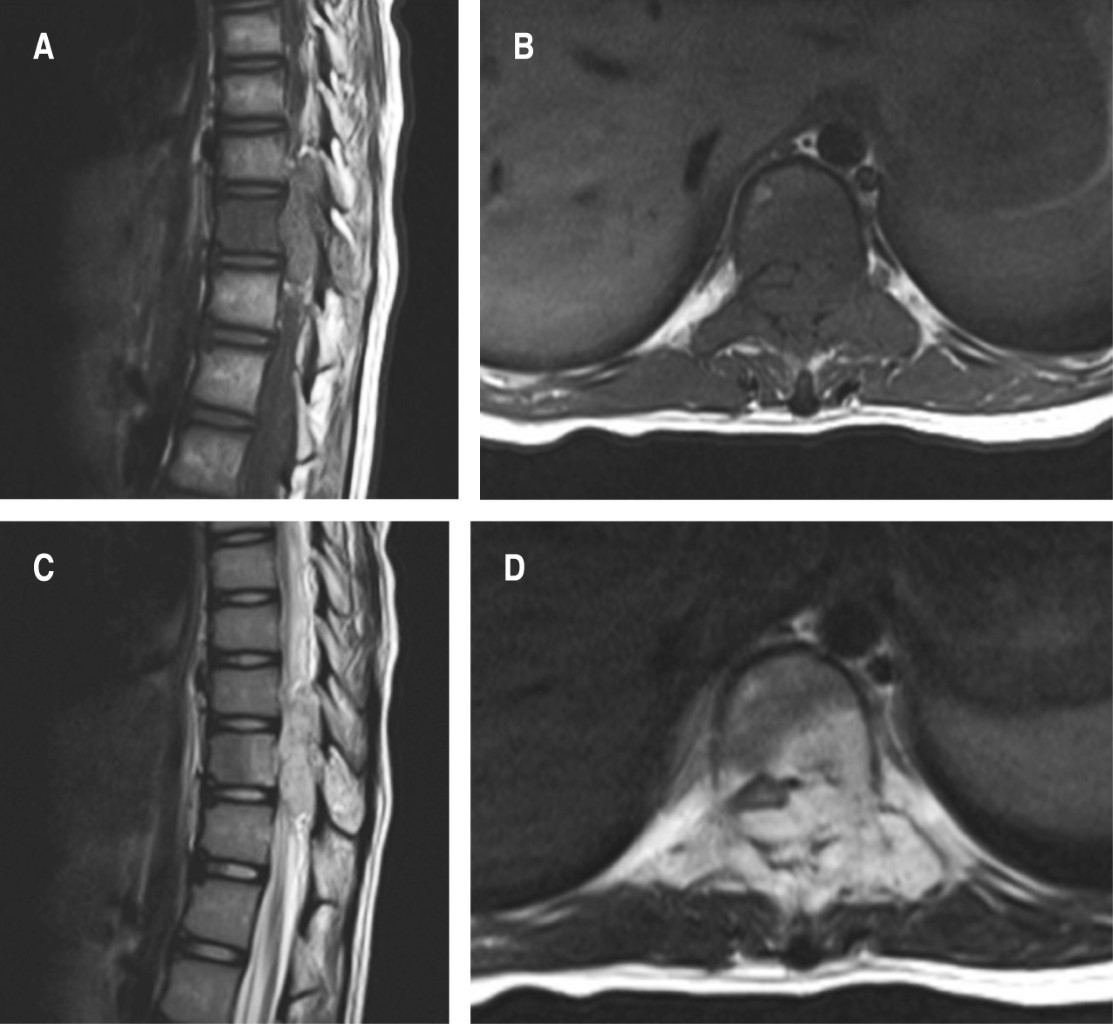

Dos semanas después reingresa a hospitalización, refiriendo lumbalgia, debilidad de extremidades inferiores y dolor abdominal secundario a realizar ejercicios de rehabilitación. A la exploración, paciente en silla de ruedas con dolor lumbar y abdominal difuso a la sedestación fuerza 1/5 de la escala de Daniels L2-S1 bilateral, disestesias en mismos niveles, signo de la navaja de muelle, hiperreflexia rotuliana y Babinski bilateral. Se realiza tomografía axial computarizada de cráneo y toracoabdominal, se identifica nivel de T10 lesión lítica que compromete hemicuerpo, pedículo y lámina izquierdos, con imagen sugerente de invasión parcial de conducto medular de predominio izquierdo (Figura 1). En la resonancia magnética nuclear simple de columna torácica se observa, en cortes coronal sagital y axial a nivel de T10, una lesión isointensa en T1 e hiperintensa en T2 de predominio izquierdo que compromete el conducto medular (Figura 2).

Se obtiene control postquirúrgico imagenológico con adecuada colocación de tornillos transpediculares y malla cilíndrica de titanio, en resonancia magnética simple se corrobora liberación del conducto medular sin cambio de intensidad de señal medular (Figura 3).